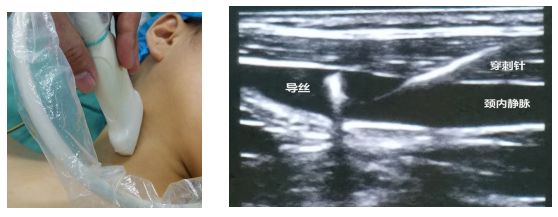

(一) 颈内静脉穿刺置管

目前,临床常用的超声引导下颈内静脉穿刺置管主要为右侧颈内静脉穿刺。在超声引导穿刺操作前,首先应使用探头查找颈内静脉和动脉,判断静脉具体位置,避免误穿动脉。

超声定位及具体穿刺方法:

⑴穿刺部位常规消毒、铺巾;

⑵超声探头的准备:首先需对探头进行消毒,在探头上涂耦合剂,用无菌套将探头及其连线包裹;

⑶ 超声图像:在患者的穿刺部位涂抹无菌石蜡油和耦合剂,保持皮肤和探头之间随时有液体存在。在颈动脉三角的上端处将探头与颈部纵轴垂直放置,即可获得颈内静脉横截面超声图像(图2)。

颈内静脉呈圆形或椭圆形,加压探头时管径显著缩小甚至闭锁。其浅部为胸锁乳突肌,内下方为颈动脉。在颈动脉三角的上端稍向下处将探头与颈部纵轴平行放置,即可获得颈内静脉纵切面超声图像(图3)。

⑷ 操作:确定探头标记侧后,距离探头0.5cm~1.0 cm,穿刺针与皮肤呈30°~45°,保证探头与穿刺针在同一平面,以确保穿刺针和静脉同时显示在屏幕上,且穿刺针需在超声视野范围内。

针尖进入血管后,回抽注射器,回血顺畅则表明穿刺针斜口完全位于颈内静脉,再进一步常规置管固定。

图2 颈动脉、颈内静脉超声横截面二维图像

图3 颈内静脉超声纵切面二维穿刺置管图像